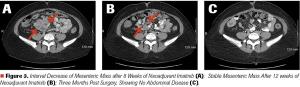

Mehmet Sitki Copur, MD, and colleagues examine the case of a 65-year-old patient with appendiceal mucinous neoplasms of the appendix who was treated with cytoreductive surgery and hyperthermic intraperitoneal chemotherapy.

ABSTRACT Gastrointestinal stromal tumors (GISTs) are rare neoplasms of the gastrointestinal tract. They commonly present with nonspecific symptoms and thus are often discovered incidentally. They are best identified by CT scan and most stain positive for CD117 (C-Kit), CD34, and/or DOG-1. Several risk stratification classification systems have been developed based on tumor size, mitotic rate, location, and perforation. Traditional chemotherapy and radiation therapy have been very ineffective, making surgery the mainstay of treatment. The discovery of mutations associated with these tumors has revolutionized the treatment approach. Imatinib mesylate, a selective tyrosine kinase receptor inhibitor, used as adjuvant or neoadjuvant therapy, has greatly improved the morbidity and mortality associated with GISTs. As the survival of patients has increased with the long-term use of targeted therapies, quality-of-life issues now have become much more relevant and have come to the forefront of care. We present a young woman who was successfully treated for GIST but now faces associated long-term adverse effects of imatinib, including the challenge of preserving fertility and the potential for childbearing.